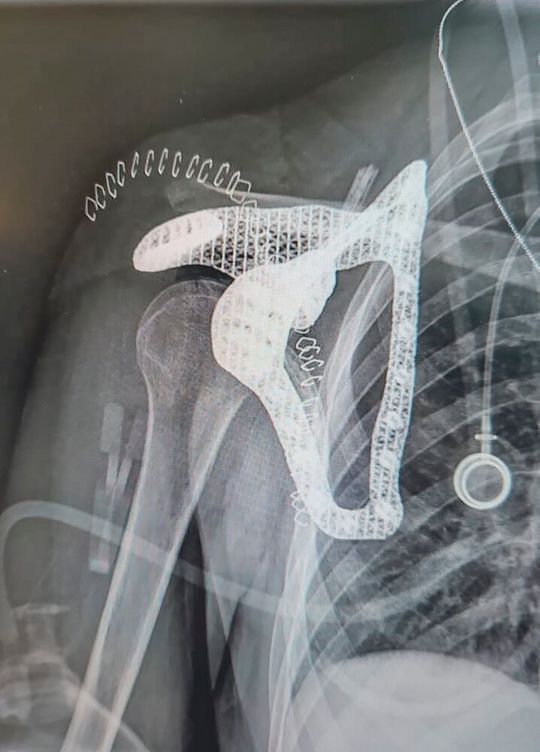

Ein Expertenteam entwickelte gemeinsam ein Scapula-Implantat aus Titan, das exakt auf die Anatomie der Patientin zugeschnitten ist. (Bild:  Tel Aviv Medical Center)

Ein Expertenteam entwickelte gemeinsam ein Scapula-Implantat aus Titan, das exakt auf die Anatomie der Patientin zugeschnitten ist.

In einem Gemeinschaftsprojekt hat ein Expertenteam des Tel Aviv Medical Center, von PTC und Hexagon ein vollständig patientenspezifisches Scapula-Implantat für eine 16-jährige Krebspatientin geschaffen. Das Team nutzte additive Fertigung und medizinische Bildgebung, um ein Scapula-Implantat aus Titan zu entwerfen und herzustellen, das exakt auf die Anatomie der Patientin zugeschnitten ist.